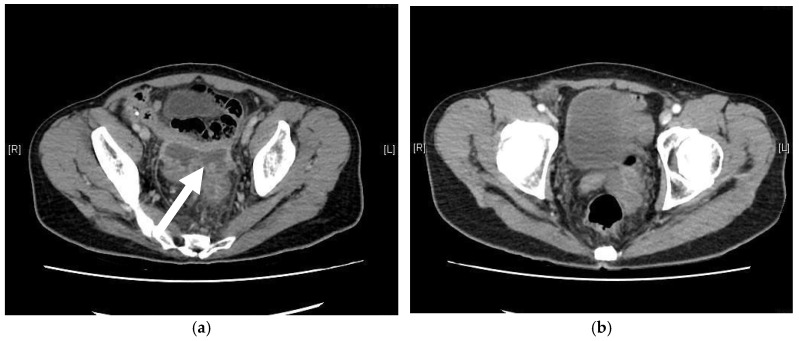

背景与目的:性别肯定手术可显著改善跨性别女性的生活质量和心理健康。在各种技术中,乙状结肠阴道成形术因其能够提供足够的阴道深度和内在润滑而被广泛应用。然而,它也有风险,新阴道穿孔是一种严重但未被报道的并发症。材料与方法:本文综述了新发阴道穿孔的病因、临床表现、诊断和治疗。我们进行文献回顾,分析报告的病例和治疗策略。此外,我们提出了一个来自我们机构的病例,以突出诊断和治疗方面的挑战。结果:新阴道穿孔是由机械损伤、缺血、感染或乙状结肠段结构缺陷引起的。常见的危险因素包括不适当的扩张、内径狭窄和血管损伤。症状从轻微的盆腔不适到腹膜炎和败血症。计算机断层扫描(CT)是诊断的金标准。轻微病例保守治疗有效,严重病例需手术修复。结论:新的阴道穿孔是罕见的,但可能危及生命。未来的研究应改进手术技术、扩张方案和组织工程解决方案。标准化指南和患者教育对于预防和改善结果至关重要。

Background and Objectives: Gender affirmation surgery significantly improves the quality of life and psychological well-being of transgender women. Among various techniques, sigmoid vaginoplasty is widely performed due to its ability to provide adequate vaginal depth and intrinsic lubrication. However, it carries risks, with neovaginal perforation being a serious yet underreported complication. Materials and Methods: This review examines the etiology, clinical manifestations, diagnosis, and management of neovaginal perforation. A literature review was conducted to analyze reported cases and treatment strategies. Additionally, we present a case from our institution to highlight diagnostic and therapeutic challenges. Results: Neovaginal perforation arises from mechanical trauma, ischemia, infection, or structural weaknesses in the sigmoid segment. Common risk factors include improper dilation, introital stenosis, and vascular compromise. Symptoms range from mild pelvic discomfort to peritonitis and sepsis. Computed tomography (CT) is the gold standard for diagnosis. Conservative management is effective in mild cases, whereas severe cases require surgical repair. Conclusions: Neovaginal perforation is rare but potentially life-threatening. Future research should refine surgical techniques, dilation protocols, and tissue engineering solutions. Standardized guidelines and patient education are essential for prevention and improved outcomes.